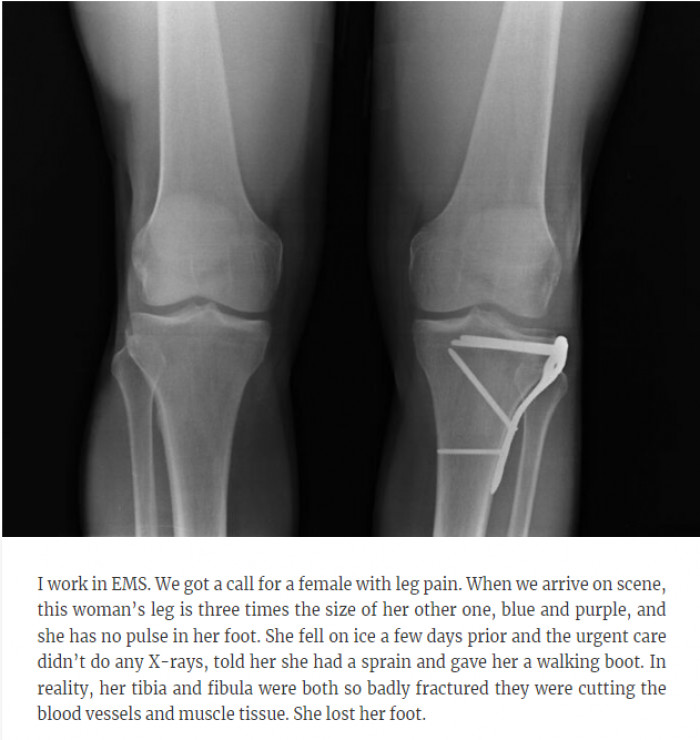

24. She lost her foot.

24. She lost her foot.Reddit/the_taco_belle, Flickr/edward stojakovic

From doctors labeling their patients as "just being dramatic" to losing a foot due to misdiagnosed injuries to a patient not being told their illness is terminal, we have these stories and many more for you below. Keep scrolling to find out all the interesting (and disturbing) details.